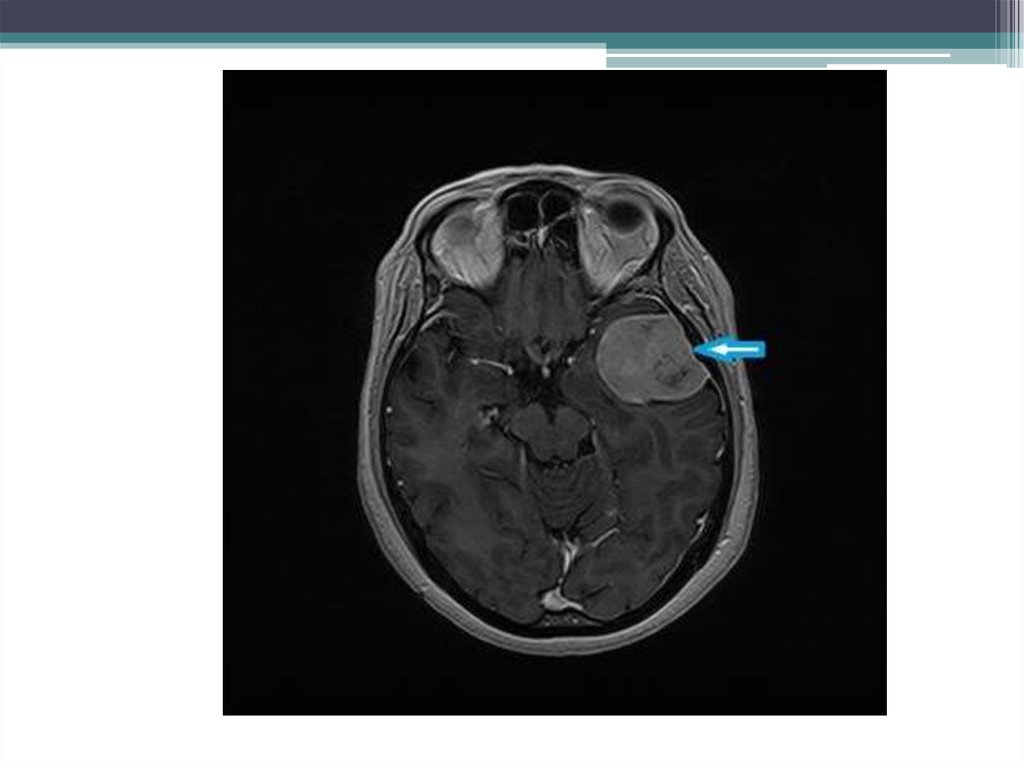

• Вестибулярная шваннома, невринома

слухового нерва, акустическая шваннома разные названия одного заболевания.

• По направлению невролога, на консультацию

в нейрохирургическое отделение обратился

пациент с жалобами на снижение остроты

слуха, шум в левом ухе, эпизоды

дискоординации.